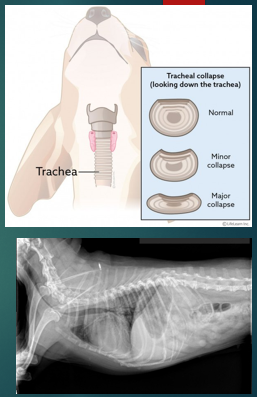

Tracheal collapse

Flattening of the tracheal rings

Commonly seen in toy/miniature breeds

Most common clinical signs is a cough - ‘goose-honk’ ‘seal-bark’

Can be elicited with pulls on lead

What is tracheal collapse?

Where cartilage tracheal rings weaken and collapse, which causes breathing difficulties, this can vary in severity